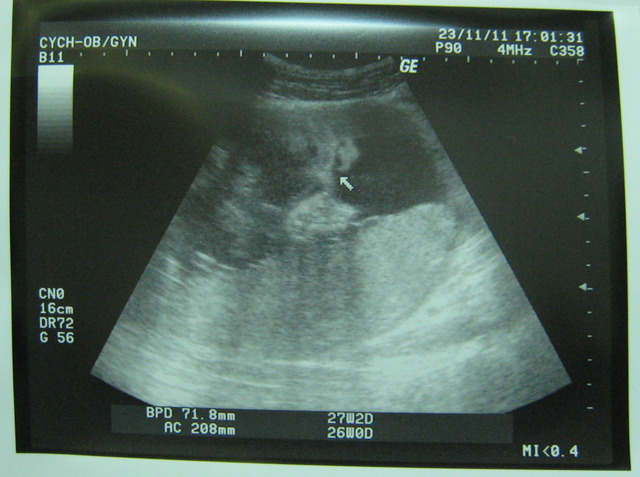

然我上拜突然肚子很痛,後不敢吃西,重少了2公斤,但瓦力是稍微成,主治他目前的重是1010公克!

最近感到胎的位置改,我以瓦力胎位正,果去就知道他的位置仍然有改。